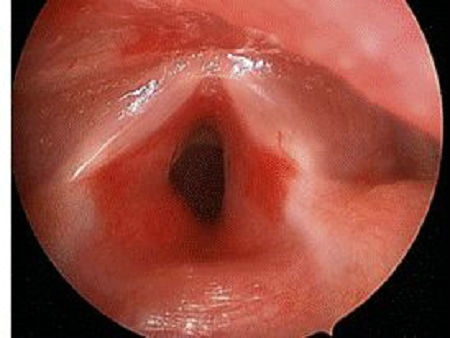

当血管瘤生长在气道(图8),出生时没有呼吸不通畅的表现,但随着患儿生长,6至8周时,可出现进食哭闹、吸气喘鸣。通过喉镜检查,可以看到瘤体阻塞气道,引起宝宝呼吸异常。

▲ 图8